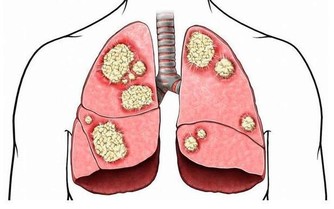

每到冬天,周圍感冒咳嗽的人就多了起來,呼吸科門診前也圍了不少前去看病的人。雖然我們都知道感冒咳嗽要去看病,也知道要吃藥打針,可是咳嗽的時候應該避免接觸什麼,這一點恐怕很多人並不知道。所以,今天就藉著這篇文章,給大家講一講咳嗽的時候,該注意避免接觸哪些東西,以及一些簡單的止咳食療方。

避免接觸六種東西

①辛辣食物

花椒、辣椒等辛辣食物,會引起咳嗽,因為辣椒中的辣椒素刺激到引發咳嗽的神經末梢,吃辛辣食物時,還會刺激咽喉部的粘膜,引發咳嗽,食物進到胃裡也會隨著胃的反流而咳嗽。

②海鮮食物

海鮮屬於異種蛋白,所以有人吃了之後會皮膚過敏,其實吃海鮮引起的呼吸道過敏也很常見。對於感冒咳嗽的患者來說,此時的呼吸道很敏感,應該避免吃海鮮。

③花生堅果

花生本身也是一個過敏原,和海鮮過敏的原理一樣,因為它當中含有的蛋白質對某些人來說會過敏,咳嗽的人也應該避免。